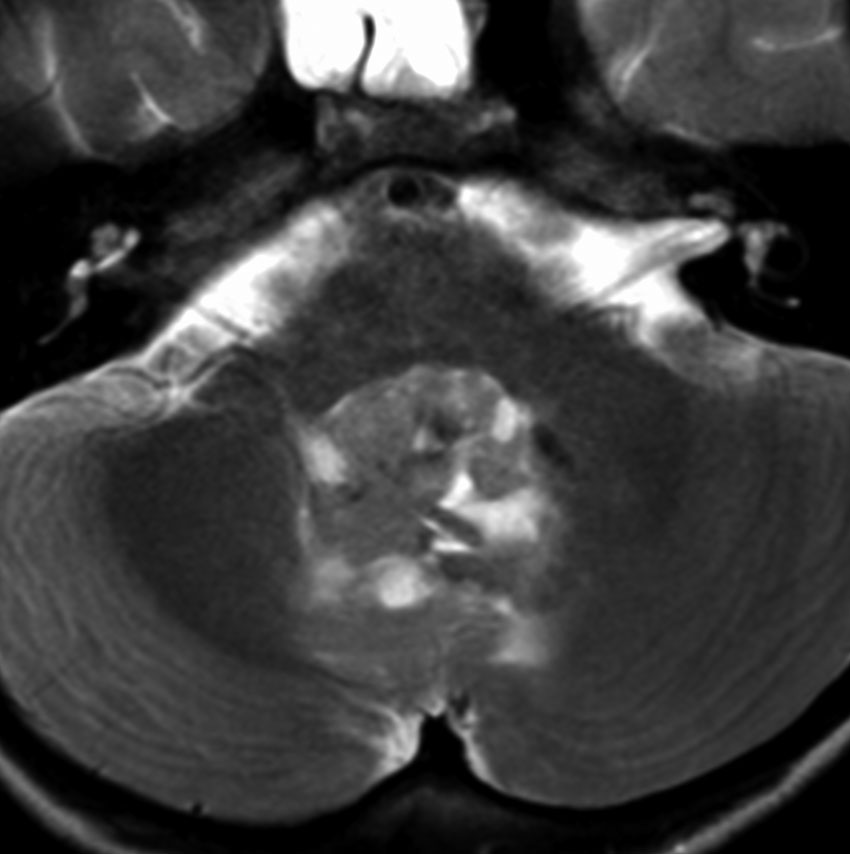

中脳視蓋毛様細胞性星細胞腫 tectal glioma(詳しくはここをクリック)

中脳視蓋グリオーマとして知られるものです。この腫瘍は基本的には,初回手術で全摘出できるのですが,現実的には,技術的に難しすぎるので部分摘出で終えることが多いでしょう。この子は,15歳の時に閉塞性水頭症のために,頭痛,嘔吐,意識障害,瞳孔不同となりました。開頭部分摘出術と第3脳室開窓術で回復して,その後にカルボプラチンとビンクリスチンの化学療法を受けました。でも腫瘍増大が止められずに,発症1年後に54グレイ30分割の放射線治療を受けています。さらにその半年後くらいから再増大しましたが,スードプログレッションと考えられました。のう胞性拡大が止まらず,発症3年後にまた再開頭手術で亜全摘出しました。